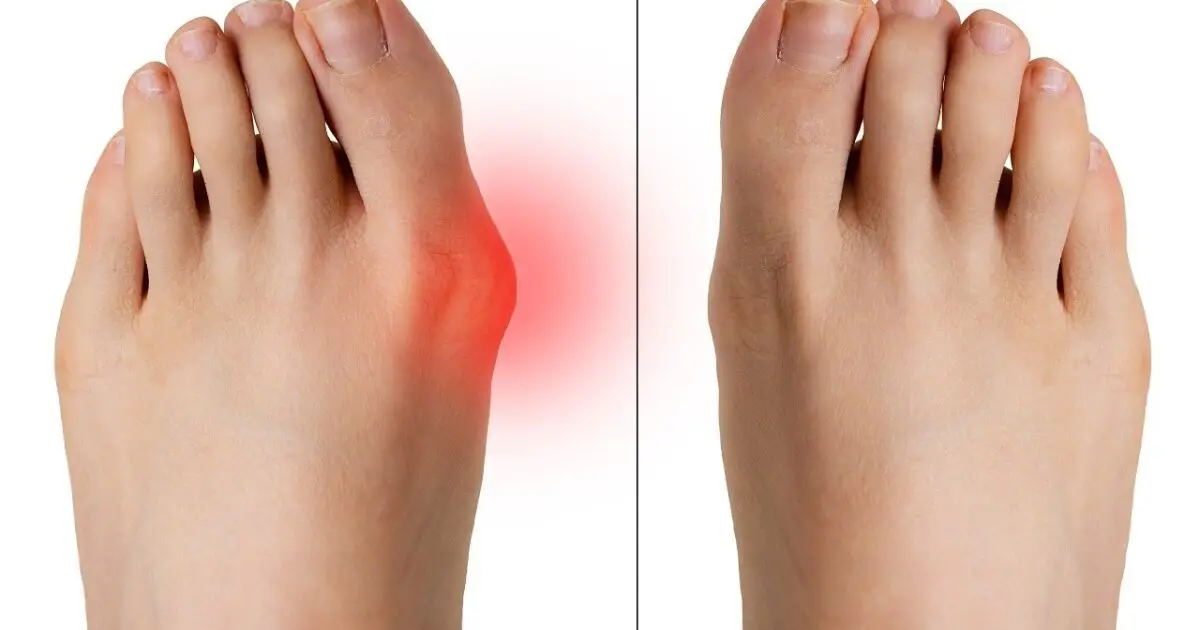

هالوکس والگوس صرفا یک انحراف ساده در انگشت شست نیست. این عارضه نتیجه یک زنجیره از تغییرات ساختاری است که معمولا از ناحیه میانی پا (Midfoot) آغاز میشود. در بسیاری از موارد، بی ثباتی در مفاصل این ناحیه و همچنین تمایل به چرخش کف پا به داخل (پرونیشن بیش از حد)، باعث میشود که اولین استخوان متاتارس (استخوان بلند پشت شست) به سمت داخل بدن منحرف شود. برای جبران این انحراف، انگشت شست پا (هالوکس) به تدریج به سمت انگشتان دیگر کج میشود. این وضعیت باعث برآمدگی سر استخوان متاتارس در لبه داخلی پا میشود که به آن بونیون میگویند.

فشار مداوم کفش های نامناسب بر روی این برآمدگی، باعث التهاب بورس (کیسه مایع محافظ مفصل) و ایجاد درد، قرمزی و تورم میشود. با گذشت زمان، این ناهماهنگی مفصلی میتواند منجر به آرتروز و تخریب غضروف مفصل متاتارسوفالانژیال (MTP) شود. درک این ماهیت پیشرونده به طراح کفش کمک میکند تا بداند که محصول او نه تنها باید به وضعیت فعلی بیمار پاسخ دهد، بلکه باید از بدتر شدن آن در آینده نیز جلوگیری کند.